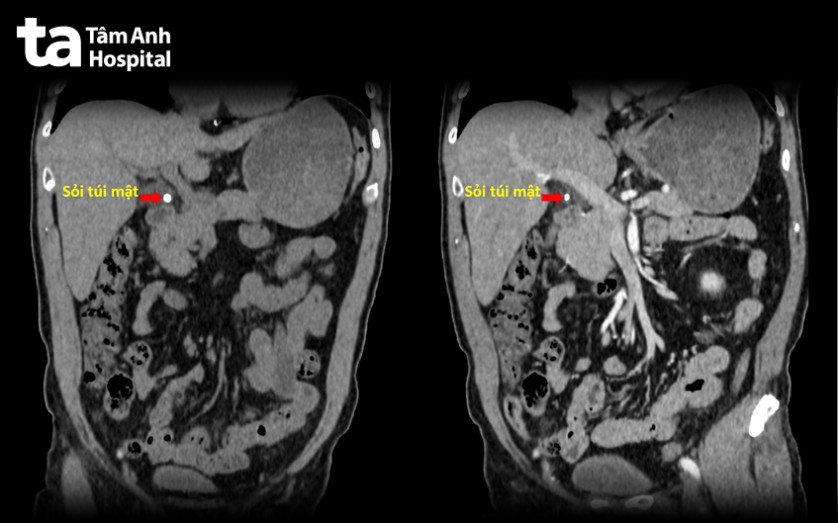

TS.BS Phạm Công Khánh, Trưởng khoa Gan – Tụy – Mật đã chỉ định ông Thuận làm một số xét nghiệm chẩn đoán. Kết quả xét nghiệm máu cho thấy tình trạng nhiễm trùng nặng, với chỉ số bạch cầu tăng hơn 18.000 (mức bình thường là 4.000-10.000/mm3 máu), hình ảnh cắt lớp vi tính (CT) gợi ý người bệnh bị viêm túi mật cấp do sỏi vùng phễu và ống túi mật.

Sau 12 giờ ngưng thuốc kháng đông, ông Thuận được tiến hành phẫu thuật nội soi cắt túi mật Phẫu thuật nội soi cắt túi mật là kỹ thuật ít xâm lấn bằng 3 vết mổ nhỏ 5 – 10mm trên bụng, sử dụng camera soi vào ổ bụng và dùng dụng cụ chuyên dụng cắt túi mật. Trong lúc phẫu thuật, bác sĩ nhận thấy có dịch đục và ít giả mạc quanh túi mật, thành túi mật hoại tử vùng đáy, lòng túi mật có 2 viên sỏi, kích thước 5 mm.